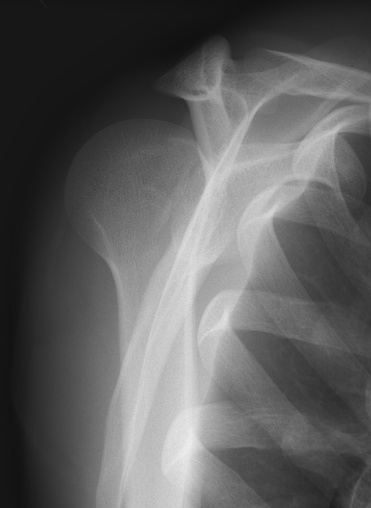

AP Xray

Abnormal overlap of humeral head on glenoid

Light-bulb sign - globular head secondary to internal rotation of the humeral head

Vacant Glenoid Cavity - > 6 mm space between humeral head and anterior rim of glenoid